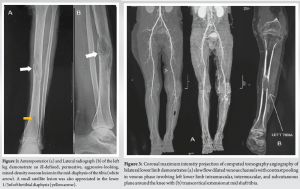

There was mild swelling in the middle of the leg with deep tenderness present. The local temperature was normal, with a full range of motion at the knee and ankle. There was no palpable lymph nodes around the popliteal or inguinal region, with no limb length discrepancy. The blood investigations, including erythrocyte sedimentation rate and C-reactive protein, were within normal limits. The patient presented to us with the radiographs and non-contrast magnetic resonance imaging (MRI). The anteroposterior (Fig. 2a) and lateral view (Fig. 2b) radiograph of the leg demonstrated a permeative intraosseous mixed density lesion (central lytic with peripheral sclerosis and presence of trabeculations/pseudo trabeculations) involving the lower half of the diaphysis, most predominant at mid diaphysis (Modified Lodwick pattern IIIB: Aggressive lesion). The mid-diaphyseal lesion appeared to be marrow-based with cortical erosion, except for the anterior cortex, which was spared. No pathological fracture or periosteal reaction was demonstrated.

The non-contrast MRI demonstrated altered marrow signal intensity in the mid and lower shaft of the tibia, which was hypointense on T1 and intermediate to hyperintense on T2-weighted images. The lesion extension into adjacent soft tissue was noted; however, no muscle edema, intermuscular fluid, or subcutaneous edema was noted. Since the patient had a congenital soft-tissue venous malformation in the distal thigh and knee, and as there were no clinical features suggestive of infection, a provisional diagnosis of intraosseous venous malformation was made. Subsequently, the diagnosis was confirmed using computed tomography (CT) angiography, which showed slow flow dilated venous channels with contrast pooling in venous phase involving left lower limb intramuscular, intermuscular, and subcutaneous plane around the knee (Fig. 3a) with transcortical extension at mid-shaft tibia (Fig. 3b).